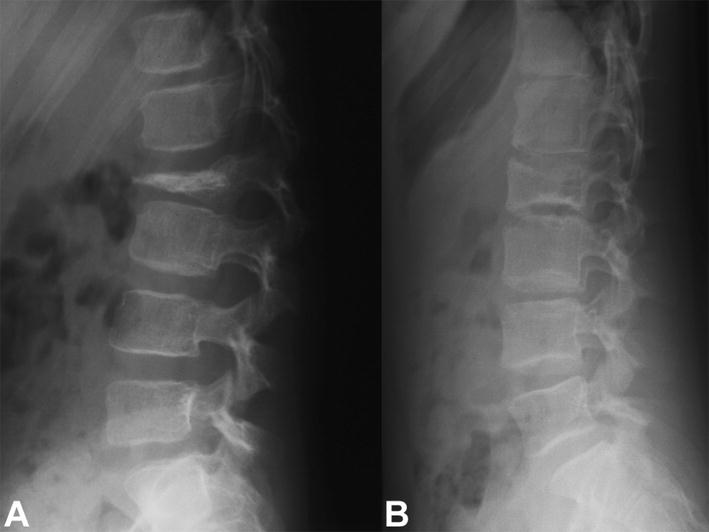

a Lateral radiograph of the lumbar spine of a 6-year-old girl with a painful osteolytic lesion of the L2 vertebral body with vertebral plana deformity. CT-guided frozen section biopsy showed eosinophilic granuloma; intralesional methylprednisolone injection was performed. b Lateral radiograph of the lumbar spine shows complete reconstitution of the lesion 7 years after diagnosis and treatment